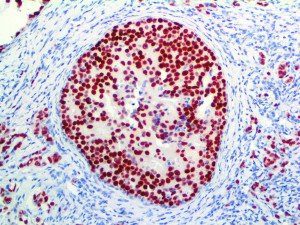

It is the ICU physician who is most likely to witness one of the deadliest manifestations of the abnormal immunological response, the cytokine storm syndrome (CSS). This response is also referred to by some as the cytokine release syndrome (CRS). CSS is characterized by continuous activation and expansion of macrophage and lymphocyte populations, which secrete large amounts of cytokines, causing the cytokine storm. This massive cytokine release is akin to hemophagocytic lymphohistiocytosis (HLH) disease, a syndrome characterized by initial unchecked and persistent activation of cytotoxic T lymphocytes and NK cells.

Clinical and laboratory manifestations of HLH include fever, enlarged liver and/or spleen, neurologic dysfunction, coagulopathy, liver dysfunction, cytopenias (i.e., low levels of erythrocytes, leukocytes, and/or platelets), hypertriglyceridemia, hyperferritinemia, hemophagocytosis, and eventually diminished NK cell activity as the immune system becomes progressively paralyzed. HLH can be familial (primary HLH) or secondary to another disease process (sHLH), such as rheumatic disease, in which it is referred to as macrophage activation syndrome (MAS, characterized by elevated ferritin).